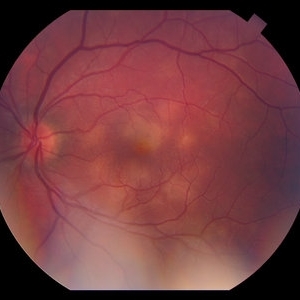

AMPPE

Apr 29 2014 by David W. Faber, MD

24-year-old female presented with central blurry vision for 3-5 days. Vision : OD 20/20, OS 20/100

Photographer: Jodi Schiele, Rocky Mountain Retina Consultants, Salt Lake City, Utah

Condition/keywords: acute multifocal placoid pigment epitheliopathy (AMPPE)